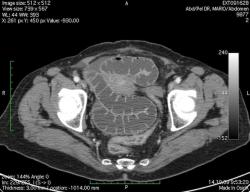

КТ брюшной полости. Женщина 73 года с жалобами на запоры.

Пациентка женщина 73 года. Предъявляет жалобы на запоры, спастические боли в брюшной полости.

ИзображениеЦиркулярное сужение в поперечной ободочной кишке. Ни это ли причина проблемм?

Новообразование в среднем отделе поперечной ободочной кишки с циркулярным сужением просвета и хронической механической толстокишечной непроходимостью. Признаков метастазирования в данной анатомической области не обнаружено. Пациент безусловно нуждается в хирургическом лечении.

Я не занимаюсь КТ, но сам характер сужения толстой кишки как-то вызывает сомнения, ракового ли он характера? Сужение то циркулярное, но больно уж ровненькое и нет признаков инфильтрации вокруг (хотя рак, конечно может иметь и такой вид). Ну, думаю dr.Mario со временем откроет карты и будет дана гистология.

Циркулярная стенозирующая опухоль (аденокарцнома) толстого кишечника; с типичной КТ презентацией и признаками обструкции. Пациентка была оперирована на второй день после КТ.